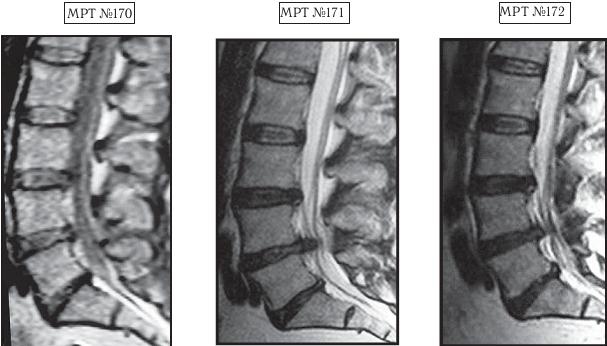

На МРТ № 168 наблюдается состояние поясничного отдела позвоночника: секвестрированная грыжа межпозвонкового диска в сегменте LIV-LV с разрывом задней продольной связки, отрывом фрагмента секвестра с его дорсальной миграцией, абсолютный стеноз спинномозгового канала. Такое состояние — последствия лечения протрузии межпозвонкового диска с применением хиропрактической техники манипуляций на позвоночнике (мануальная терапия). На МРТ № 169 — состояние поясничного отдела позвоночника после лечения методом вертеброревитологии: отсутствие грыжи межпозвонкового диска в сегменте LIV-LV, отсутствие стеноза спинномозгового канала. Разные люди, разные случаи. В следующем примере столь значительное ухудшение состояния здоровья пациента было спровоцировано его индивидуальными занятиями на приспособлении для вытяжения позвоночника. А всё началось с банального желания избавиться от «стартовых» болей в пояснице. ![]() На МРТ № 170 наблюдается состояние поясничного отдела позвоночника: ретроспондилолистез LV (соскальзывание позвонка относительно другого позвонка), протрузии межпозвонковых дисков в сегментах LII—LIV и LIV-LV На МРТ № 171 наблюдается состояние поясничного отдела позвоночника: ретроспондилолистез LV увеличение протрузии межпозвонкового диска в сегменте LIII-LIV, образование секвестрированной грыжи межпозвонкового диска в сегменте LIV-LV с разрывом задней продольной связки, абсолютный стеноз на этом уровне. На МРТ № 172 — состояние поясничного отдела позвоночника в середине первого курса лечения методом вертеброревитологии (после двух недель от начала лечения): наблюдается положительная динамика, выраженная ретрузия секвестра грыжи межпозвонкового диска в сегменте LIV-LV, визуально прослеживается увеличение высоты межпозвонкового диска в том же сегменте, что свидетельствует о начавшемся активном процессе его восстановления, значительное уменьшение стеноза спинномозгового канала на данном уровне. «Стартовые» боли в пояснице в основном проявлялись, когда данный человек выходил из автомобиля. В течение нескольких минут они ему «мешали распрямить спину». Потом, правда, исчезали и могли вновь напомнить о себе после длительного сидения в кресле или в автомобиле. Но так как пациент в силу своих служебных обязанностей вынужден много сидеть (проводить многочасовые совещания, работать с бумагами и так далее), то, естественно, эти боли его раздражали. Как говорится, чрезмерная бюрократия вредна не только для здоровой экономики страны, но и для здоровья самого бюрократа. После того как ему сделали снимок (МРТ № 170) и выяснили, что данные боли возникают вследствие развития спондилолистеза, то, естественно, пациенту предложили операцию с целью стабилизации поражённого сегмента. Не поверив нашим эскулапам (нет пророка в своём Отечестве), пациент отправился в знаменитую клинику за границу, где «светилы» зарубежной медицины (в основном наши бывшие соотечественники) также подтвердили необходимость в оперативном разрешении данной ситуации. Однако пациент, хотя досконально и не разбирался в вопросах заболеваний позвоночника, но зато умел делать выводы из чужих ошибок. Менее двух лет назад его коллега после операции на позвоночнике (кстати, в той же зарубежной клинике) променял солидную должность и кресло «большого начальника» на инвалидность, поэтому этот человек оперироваться не стал и решил пойти другим путём. Приехав домой, он начитался различной рекламы по лечению остеохондроза и его осложнений и выбрал для себя наиболее удобный способ лечения, который вполне устраивал его в режиме служебной деятельности. Обратившись в специализированный медицинский центр по лечению остеохондроза, он приобрёл там специальное приспособление для вытяжения позвоночника и получил от специалистов данного центра комплекс упражнений на нём. Месяц добросовестных тренировок, совмещённых с вытяжением позвоночника (согласно рекомендациям специалистов!) дал свои закономерные результаты. «Стартовые» боли в пояснице при подъёме, из-за которых и началась вся эта история, пациента уже не волновали, поскольку он вообще перестал не только сидеть, но даже ходить. Естественно, начались и другие проблемы в позвоночнике. Следующий месяц в стационаре неврологии (в хирургию упорно не хотел) дали положительные результаты: острые боли постепенно утихали от воздействия сильных обезболивающих препаратов. Пациент смог вставать на ноги, с посторонней помощью проходить от пяти до десяти метров. Сделали снимок (МРТ № 171), на котором выявили секвестрированную грыжу межпозвонкового диска в сегменте LIV—LV с разрывом задней продольной связки. До этого времени ему не могли провести обследования из-за некупируемых болей, а от наркоза он отказывался. Врачи диагностического центра, проводившие МРТ-обследование, посоветовали ему обратиться ко мне. В этот же день, когда больного привезли ко мне на приём, я взялся за эту работу. Через две недели лечения методом вертеброревитологии данный пациент смог самостоятельно приезжать на автомобиле (за рулём). По своей инициативе он сразу сделал ещё одно МРТ (результат интересный, МРТ № 172), на котором можно наблюдать процесс обратного движения грыжи, то есть когда фрагменты выпавшего межпозвонкового диска «заходят» обратно в межпозвонковый диск. Другими словами — процесс ретрузии секвестра грыжи межпозвонкового диска в сегменте LIV-LV а также активный процесс восстановления самого диска. ![]() На МРТ № 173 (увеличенный фрагмент МРТ,№ 171) наблюдается секвестрированная грыжа межпозвонкового диска в сегменте LIV-LV с разрывом задней продольной связки, абсолютный стеноз на этом уровне. На МРТ № 174 (увеличенный фрагмент МРТ № 172) наблюдается состояние межпозвонкового диска в середине первого курса лечения методом вертеброревитологии (после двух недель от начала лечения): положительная динамика, выраженная ретрузия секвестра грыжи межпозвонкового диска в сегменте LIV-LV Вот ещё одни снимки МРТ другого пациента, которые наглядно демонстрируют процесс ретрузии грыжи диска. ![]() На МРТ № 175 наблюдается состояние поясничного отдела позвоночника: компенсированная протрузия, грыжа Шморля в сегменте LIV-LV, спондилёз, гипертрофия задней и передней продольных связок, грыжа межпозвонкового диска сегменте LV—SI, стеноз спинномозгового канала. |